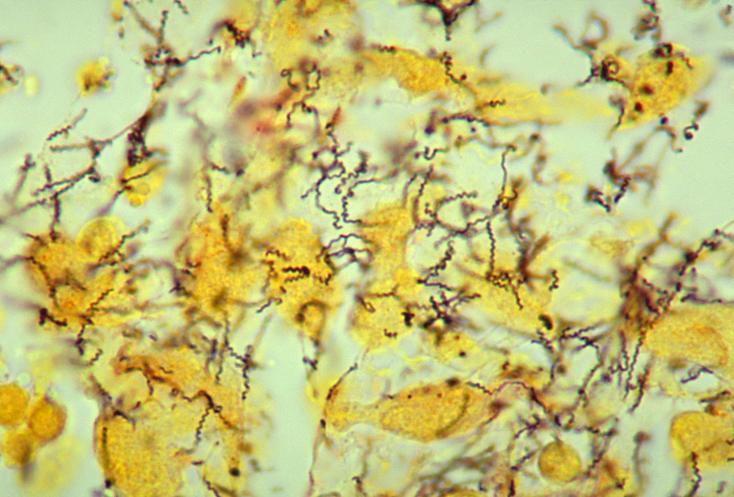

Siphilis adalah sebuah infeksi sistemik yang disebabkan oleh treponem…

Siphilis adalah sebuah infeksi sistemik yang disebabkan oleh treponem…

Siphilis adalah sebuah infeksi sistemik yang disebabkan oleh treponem…

Siphilis adalah sebuah infeksi sistemik yang disebabkan oleh treponem…